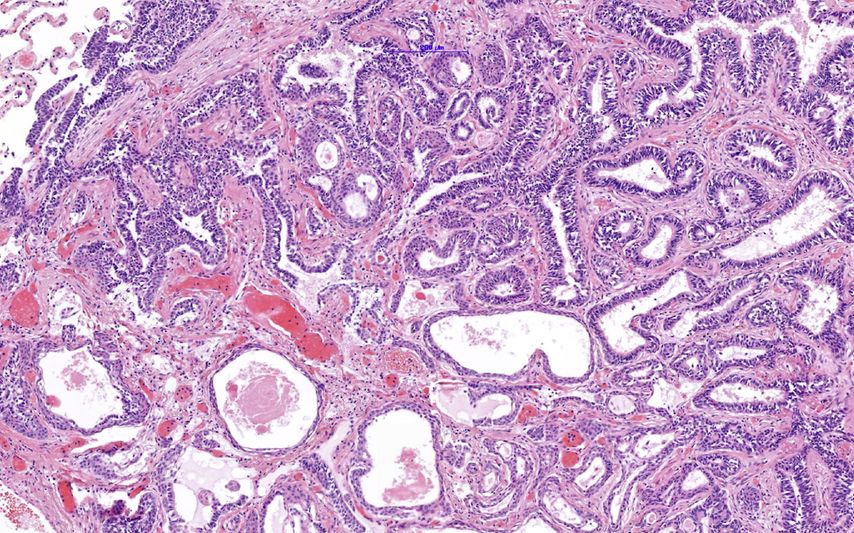

Abb. 1:Im Übersichtsbild kommt der kleine Knoten deutlich hervor. Maßstab 5000µm

Abb. 3:Übersicht mit plattenepithelial differenzierten Zellen (oben) und Schleimproduktion/Freisetzung in der unteren Hälfte. Maßstab 200µm

Der ziliäre papilläre mukonoduläre Tumor der Lunge ist eine neue Entität, der eine charakteristische Morphologie aufweist (Abb. 1–4). Aufgrund der bisherigen Berichte kann von einer geringen Malignität ausgegangen werden. Die molekularen Signaturen lassen aber die Möglichkeit einer Rezidivierung und eventuell sogar einer Metastasierung offen.Dementsprechend kann eine Prognose nicht mit Sicherheit abgegeben werden. Eine engmaschige Kontrolle in den ersten fünf Jahre nach Diagnose ist zu empfehlen.